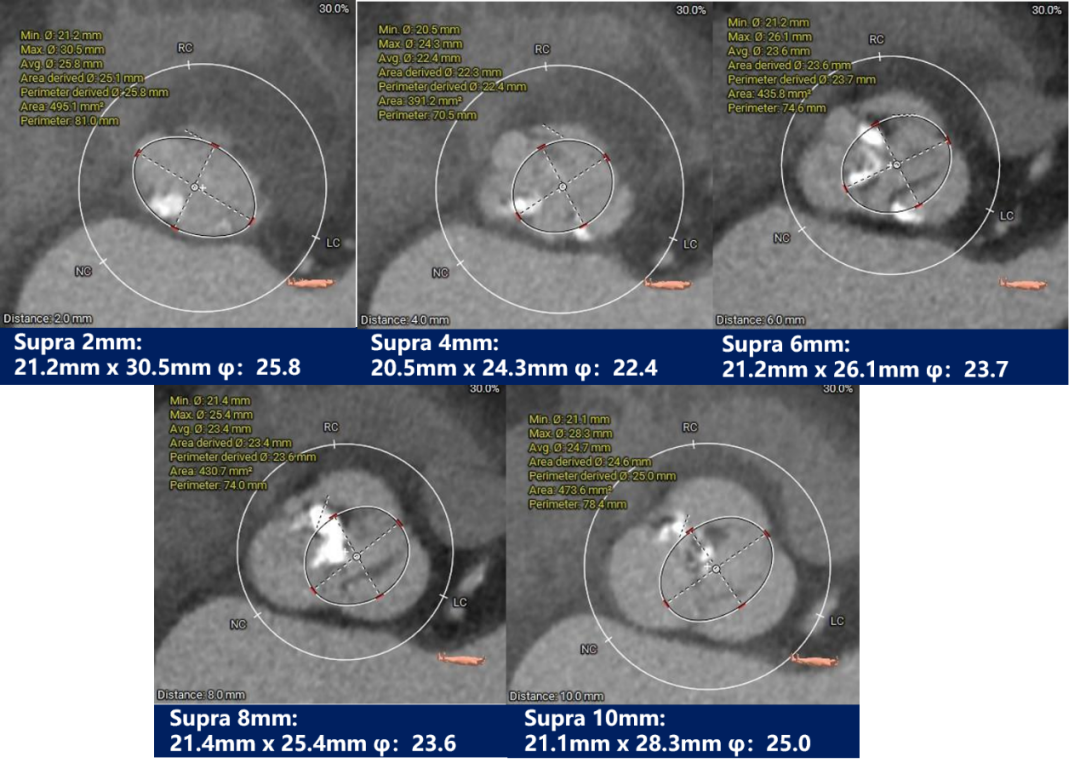

瓣上测量:

瓣上测量:瓣叶中度钙化,钙化分布不均匀,主要分布于右无交界融合处,且无窦下钙化延伸至LVOT。